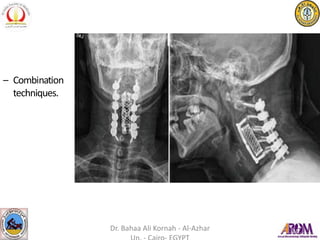

– Combination

techniques.